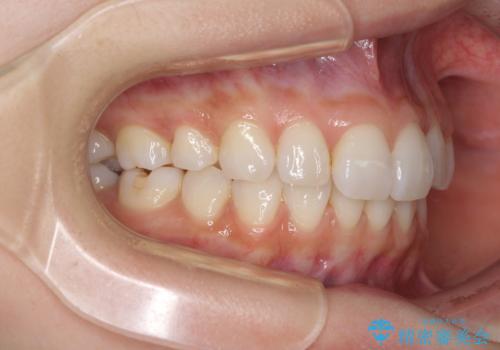

矯正治療の後戻り インビザラインによる再矯正治療

- 以前ワイヤー装置にて行った抜歯矯正の後戻りを気にして来院された患者様です。

前歯のデコボコにより、やや口元が突出した印象となっていたため、口元も引っ込めることとしました。

上下顎前歯に積極的にIPR(歯と歯の間を削る)を行い、インビザラインを用いて治療していくこととしました。

デコボコが解消されるのはもちろんのこと、突出感のあった前歯を引っ込めることができ、患者様には大変満足していただきました。